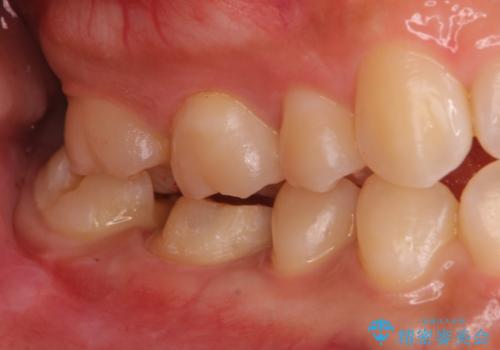

- 右下の保険治療での樹脂の劣化、および歯と歯の間の虫歯をセラミックのつめもので治療しました。

右下6番はセラミックのアンレーが入っていましたが、強度の問題もあり、やり直し後はクラウンとしました。